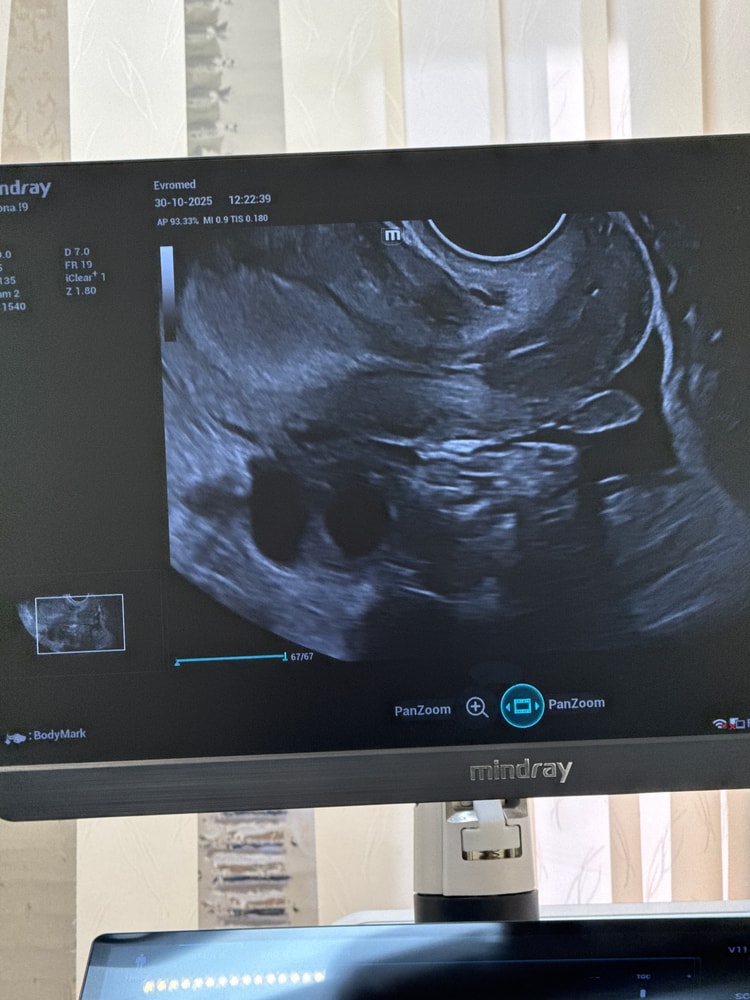

Анастасия , вот, как будто бы реально два плодных яйца. Может быть у другого специалиста переделать УЗИ? Изображение

Анастасия , это фотография матки или яичника?

Молодая мама Леся маленького принца Александра, как я поняла яичника, перед тем как закончить она сказала «ой а что тут в правом»

Анастасия , тогда да, скорее всего это либо фолликулы, либо жёлтое тело. Если два жёлтых тела, есть вероятность многоплодной беременности

Молодая мама Леся маленького принца Александра, Изображение

Анастасия , если она предполагает жидкостное образование в правом яичнике, могла сфотографировать его для врача акушера-гинеколога, как подтверждение УЗИ-заключения. Лучше переделать УЗИ в другом месте

05.11.2025